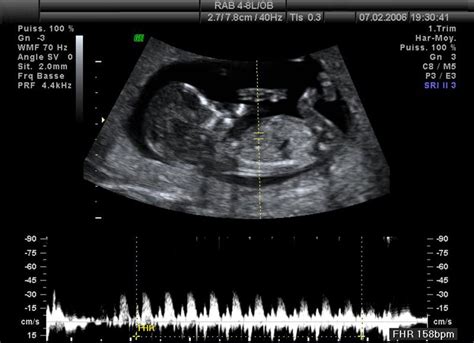

- Ultrazvukové vyšetrenie: Ultrazvuk je nevyhnutný na vizualizáciu tehotenstva, určenie jeho umiestnenia (v maternici alebo mimo nej) a posúdenie vývoja plodu. Na začiatku tehotenstva nemusí byť tehotenstvo viditeľné na ultrazvuku, aj keď hladina hCG naznačuje tehotenstvo. Vtedy je potrebné opakované sledovanie.